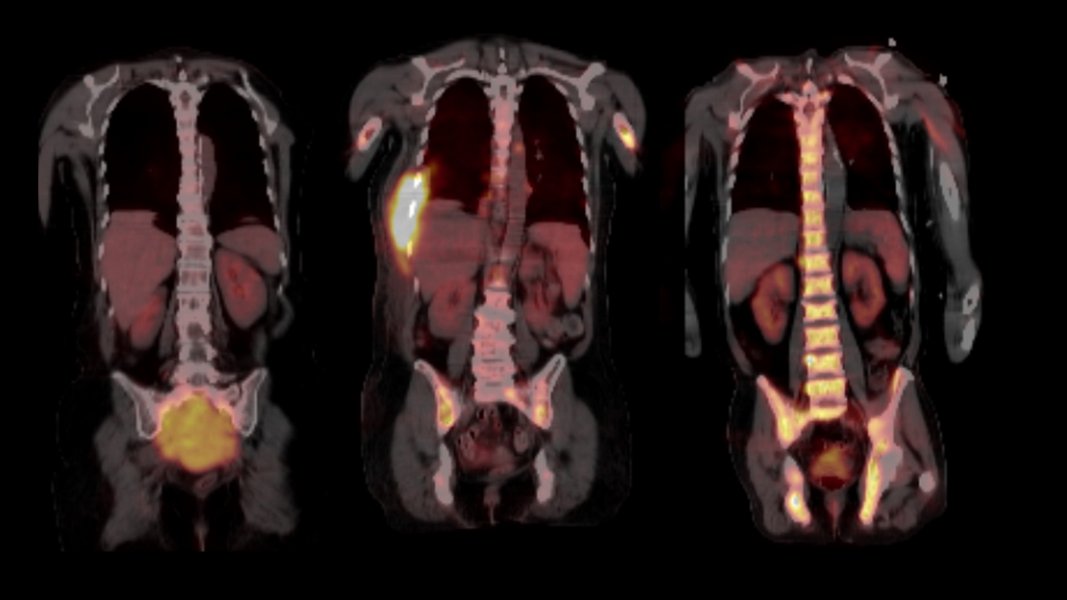

Unterschiedliche Tumorzellen an verschiedenen Orten

Ihre Arbeit basiert auf Proben aus dem weltweit größten Myelom-Zentrum an der University of Arkansas for Medical Sciences in Little Rock (USA), wo beide Wissenschaftler mehrere Jahre lang gemeinsam geforscht haben. Im Jahr 2017 hatten sie bereits in Nature Communications über die räumliche, genomische Heterogenität der Tumorzellen berichtet. „Bis vor kurzem wurden in der Forschung immer nur einzelne Knochenmarkproben aus dem Becken untersucht. Ein erwachsener Mensch verfügt jedoch über etwa fünf Kilogramm Knochenmark, die sich über das gesamte Skelettsystem verteilen. Somit ließ sich die Evolution der Tumorzellen bislang gar nicht ausreichend abbilden," schildert Privatdozent Dr. Leo Rasche, Erstautor der Studie und Juniorgruppenleiter am Mildred-Scheel-Nachwuchszentrum (MSNZ) für Krebsforschung am Uniklinikum Würzburg die Ausgangslage. Die Forscher und ihre Teams haben nun 140 Proben analysiert, die in einem Zeitraum von bis zu 13 Jahren aus verschiedenen Skelettlokalisationen von 24 Myelom-Patientinnen und -Patienten gewonnen wurden. Dazu wurden zum Teil bildgebende Verfahren wie Magnetresonanztomografie (MRT) und Positronen-Emissions-Tomografie (PET) genutzt, um die Tumorherde, die so genannten fokalen Läsionen abzubilden.

Fokale Läsionen sind die Hotspots der Tumor-Evolution

Durch die Nutzung der bildgebenden Verfahren kamen die Wissenschaftler zur ersten wichtigsten Erkenntnis: Dass die entscheidenden Schritte der Tumor-Evolution oft außerhalb des Beckens, in den Tumorherden ablaufen. „In den fokalen Läsionen haben wir Mutationen gefunden, die wir sonst nirgendwo gesehen haben und die aggressiver erschienen, da sie in die Kategorie der so genannten Cancer Driver Genes - genetische Veränderungen, die das Krebswachstum ankurbeln - fielen. Die Eigenschaften der Tumorzellen können sich jedoch nach jeder Therapie-Linie unterscheiden, sogar dann, wenn sich die Tumormasse während der Therapie nicht verändert hat. Wir schließen daraus, dass regelmäßige biologische Untersuchungen des Myeloms während der Therapie erfolgen müssen, wenn die Erkrankung gezielt behandelt werden soll", resümiert Niels Weinhold, Leiter der Translationalen Myelom-Forschung am Universitätsklinikum Heidelberg.

Generell sei bei allen Behandlungen, auch nach vermeintlich erfolgreicher Therapie eine regelmäßige Untersuchung vonnöten. „Wir bitten unsere Patientinnen und Patienten auch in der Remission alle drei Monate zu uns, um eine Kontrolle im Blut durchzuführen und gegebenenfalls mittels MRT oder PET zu prüfen, ob es fokale Läsionen gibt", schildert Leo Rasche. Unbehandelt versterben die Betroffenen in der Regel innerhalb eines Jahres.